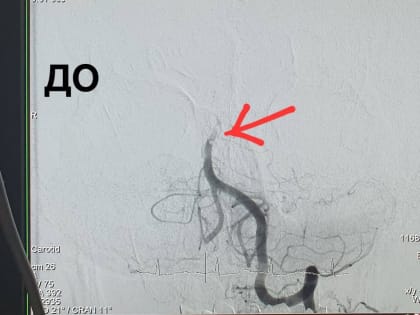

Результат томографии. Источник: Минздрав Оренбургской области В Оренбурге хирурги провели операцию под названием «Реканализация, аспирационная тромбэкстракция (удаление тромбов) из базилярной артерии» пациенту,

В Оренбурге рентген-хирурги Алексей Демин и Эдуард Гаврилов удалили 59-летнему пациенту тромб в базилярной артерии мозга.

Рентгенхирурги областной клинической больницы имени Войнова впервые в регионе выполнили операцию по удалению тромбов из базилярной артерии, снабжающей кровью задние отделы мозга.